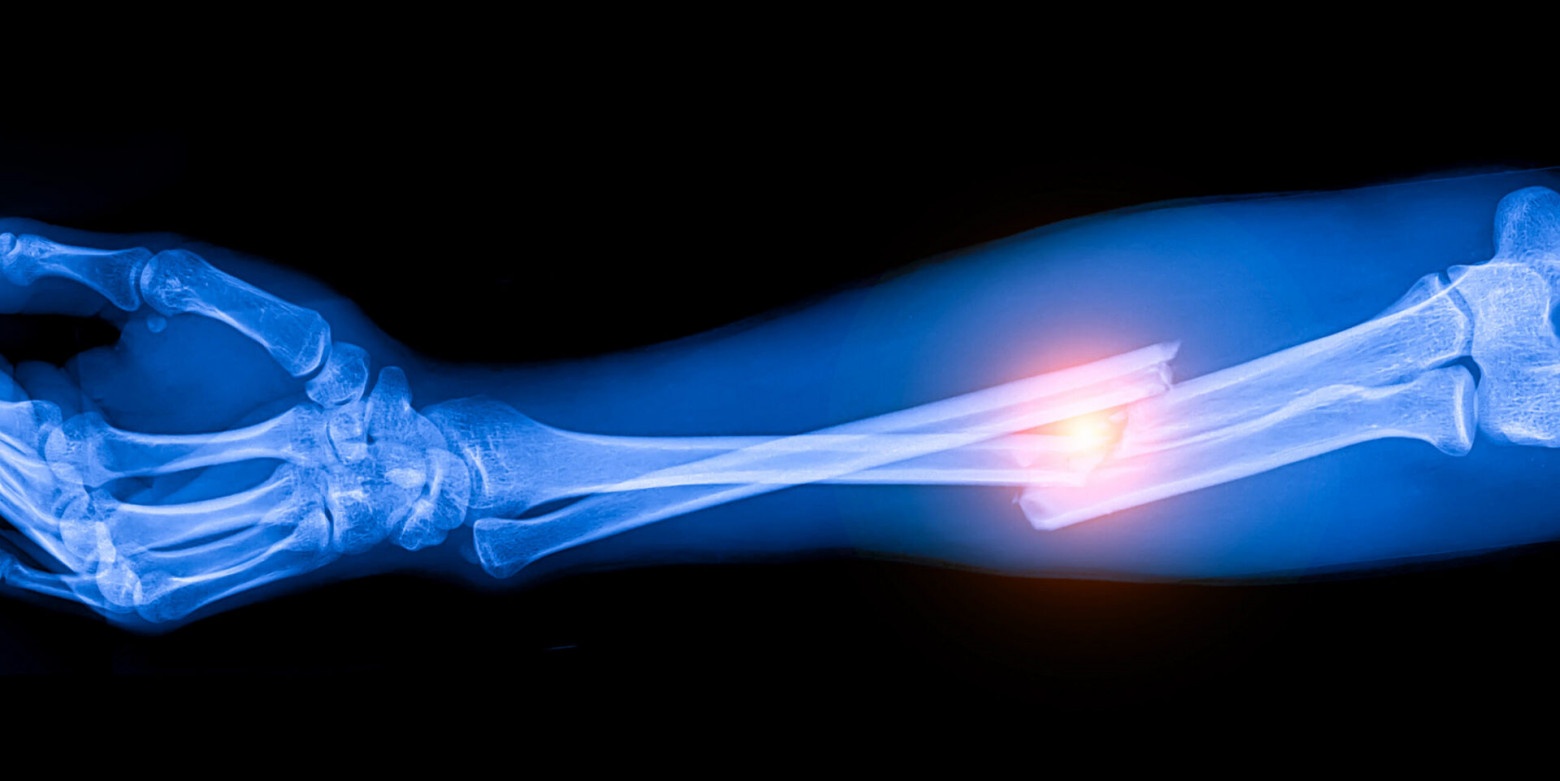

Перелом кости является одной из самых распространенных травм, которые чаще всего довольно легко лечатся без необходимости в хирургическом вмешательстве или использовании специальных металлических, костных или керамических имплантов. Однако в особо тяжких случаях без этого не обойтись. Как и любое другое инвазивное вмешательство, подобное лечение сопряжено с рядом рисков как в процессе вмешательства, так и во время восстановительного периода. Ученые из Швейцарской высшей технической школы Цюриха разработали гидрогелевые имплант, состоящий на 97% из воды и изготавливаемый с помощью лазера, которые может стать крайне эффективной заменой классических имплантов для лечения сложных переломов. Как изготавливался этот имплант, как именно он работает, и насколько он эффективен? Ответы на эти вопросы мы найдем в докладе ученых.

В рассмотренном нами сегодня труде ученые создали новый метод производства гидрогелевого композита, который может быть использован в качестве альтернативы имплантам, применяемым для заживления сложных переломов костей.

Переломы не являются редким видом травмы. Чаще всего процесс заживления протекает без необходимости в хирургическом вмешательстве. В более сложных случаях необходимо может понадобиться использование имплантов. Современные импланты обычно изготавливаются из собственной кости пациента, называемой аутотрансплантатом, или из металлических и керамических материалов. Аутотрансплантаты требуют дополнительной операции по сбору костной ткани, что увеличивает время восстановления и риски, связанные с операцией. Металлические импланты также могут создавать проблемы, поскольку они гораздо жестче, чем естественная кость, и со временем могут расшатываться, снижая долгосрочную стабильность.

Кость, как и любая другая часть организма, является сложной и сбалансированной структурой. Она содержит бесчисленные микроскопические туннели и полости, которые необходимы для прочности и функционирования.

Успешное восстановление кости зависит от того, насколько много типов клеток сначала перемещаются в имплант, а затем работают вместе, чтобы построить новую ткань. Когда кость ломается, организм не сразу создает твердую ткань. Вместо этого он формирует мягкую, проницаемую структуру. Этот временный каркас позволяет иммунным и регенеративным клеткам проникать внутрь, одновременно доставляя питательные вещества. Сеть фибрина удерживает эти клетки вместе. Со временем этот гибкий каркас медленно превращается в твердую кость.